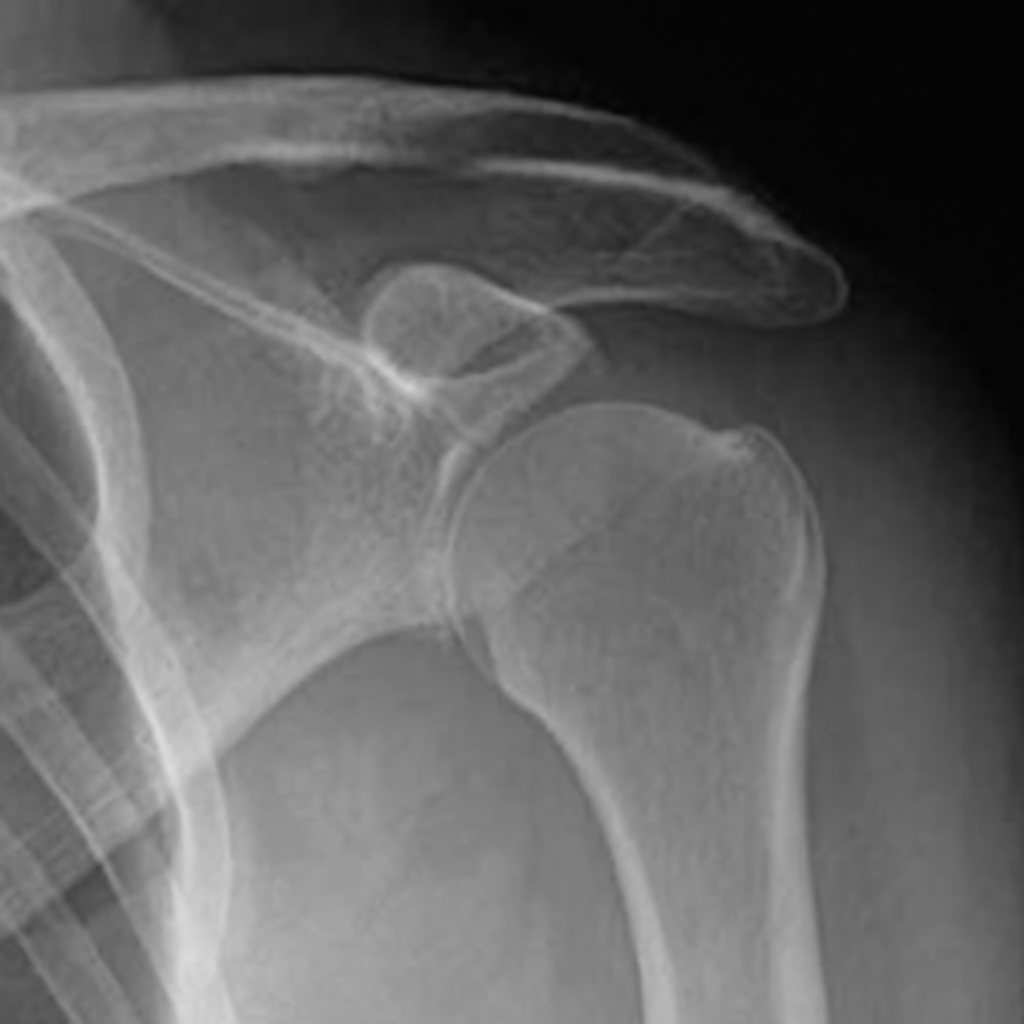

Die Schulter ist das beweglichste Gelenk des menschlichen Körpers. Gleichzeitig macht sie diese Beweglichkeit auch besonders anfällig für Instabilitäten und Verrenkungen. Eine Schulterluxation, also das vollständige Ausrenken des Gelenks, ist oft die Folge eines Unfalls oder einer plötzlichen Krafteinwirkung. Bei wiederholten Ausrenkungen spricht man von einer chronischen Schulterinstabilität.

Nach der ersten Luxation bleibt häufig ein Gefühl der Unsicherheit in der Schulter zurück. Sportliche Aktivitäten oder sogar alltägliche Bewegungen können zur erneuten Ausrenkung führen. Diese Instabilität kann langfristig zu Knorpelschäden, Gelenkverschleiß und einer frühzeitigen Instabilitätsarthrose des Schultergelenkes führen.

Die moderne Schulterchirurgie bietet effektive Behandlungsmöglichkeiten. Je nach Ausmaß der Instabilität kommen arthroskopische Verfahren zum Einsatz, bei denen verletzte Strukturen wie die Gelenkkapsel oder das Labrum (Gelenklippe) rekonstruiert werden. Liegen grösser Knochendefekt der Gelenkpfanne vor oder leiden Sie an einer Rezidiv (Rückfall)-Instabilität sind oft Knochenblock Operationen notwendig wo ein Knochenblock in den Pfannendefekt eingesetzt wird um die natürliche Form der Gelenkenkpfanne und damit die natürliche Stabilität des Gelenks wiederherzustellen und zukünftige Luxationen zu verhindern.